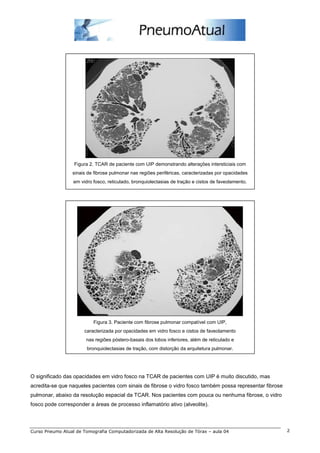

Figura 2. TCAR de paciente com UIP demonstrando alterações intersticiais com

sinais de fibrose pulmonar nas regiões periféricas, caracterizadas por opacidades

em vidro fosco, reticulado, bronquiolectasias de tração e cistos de faveolamento.

Figura 3. Paciente com fibrose pulmonar compatível com UIP,

caracterizada por opacidades em vidro fosco e cistos de faveolamento

nas regiões póstero-basais dos lobos inferiores, além de reticulado e

bronquiolectasias de tração, com distorção da arquitetura pulmonar.

O significado das opacidades em vidro fosco na TCAR de pacientes com UIP é muito discutido, mas

acredita-se que naqueles pacientes com sinais de fibrose o vidro fosco também possa representar fibrose

pulmonar, abaixo da resolução espacial da TCAR. Nos pacientes com pouca ou nenhuma fibrose, o vidro

fosco pode corresponder a áreas de processo inflamatório ativo (alveolite).